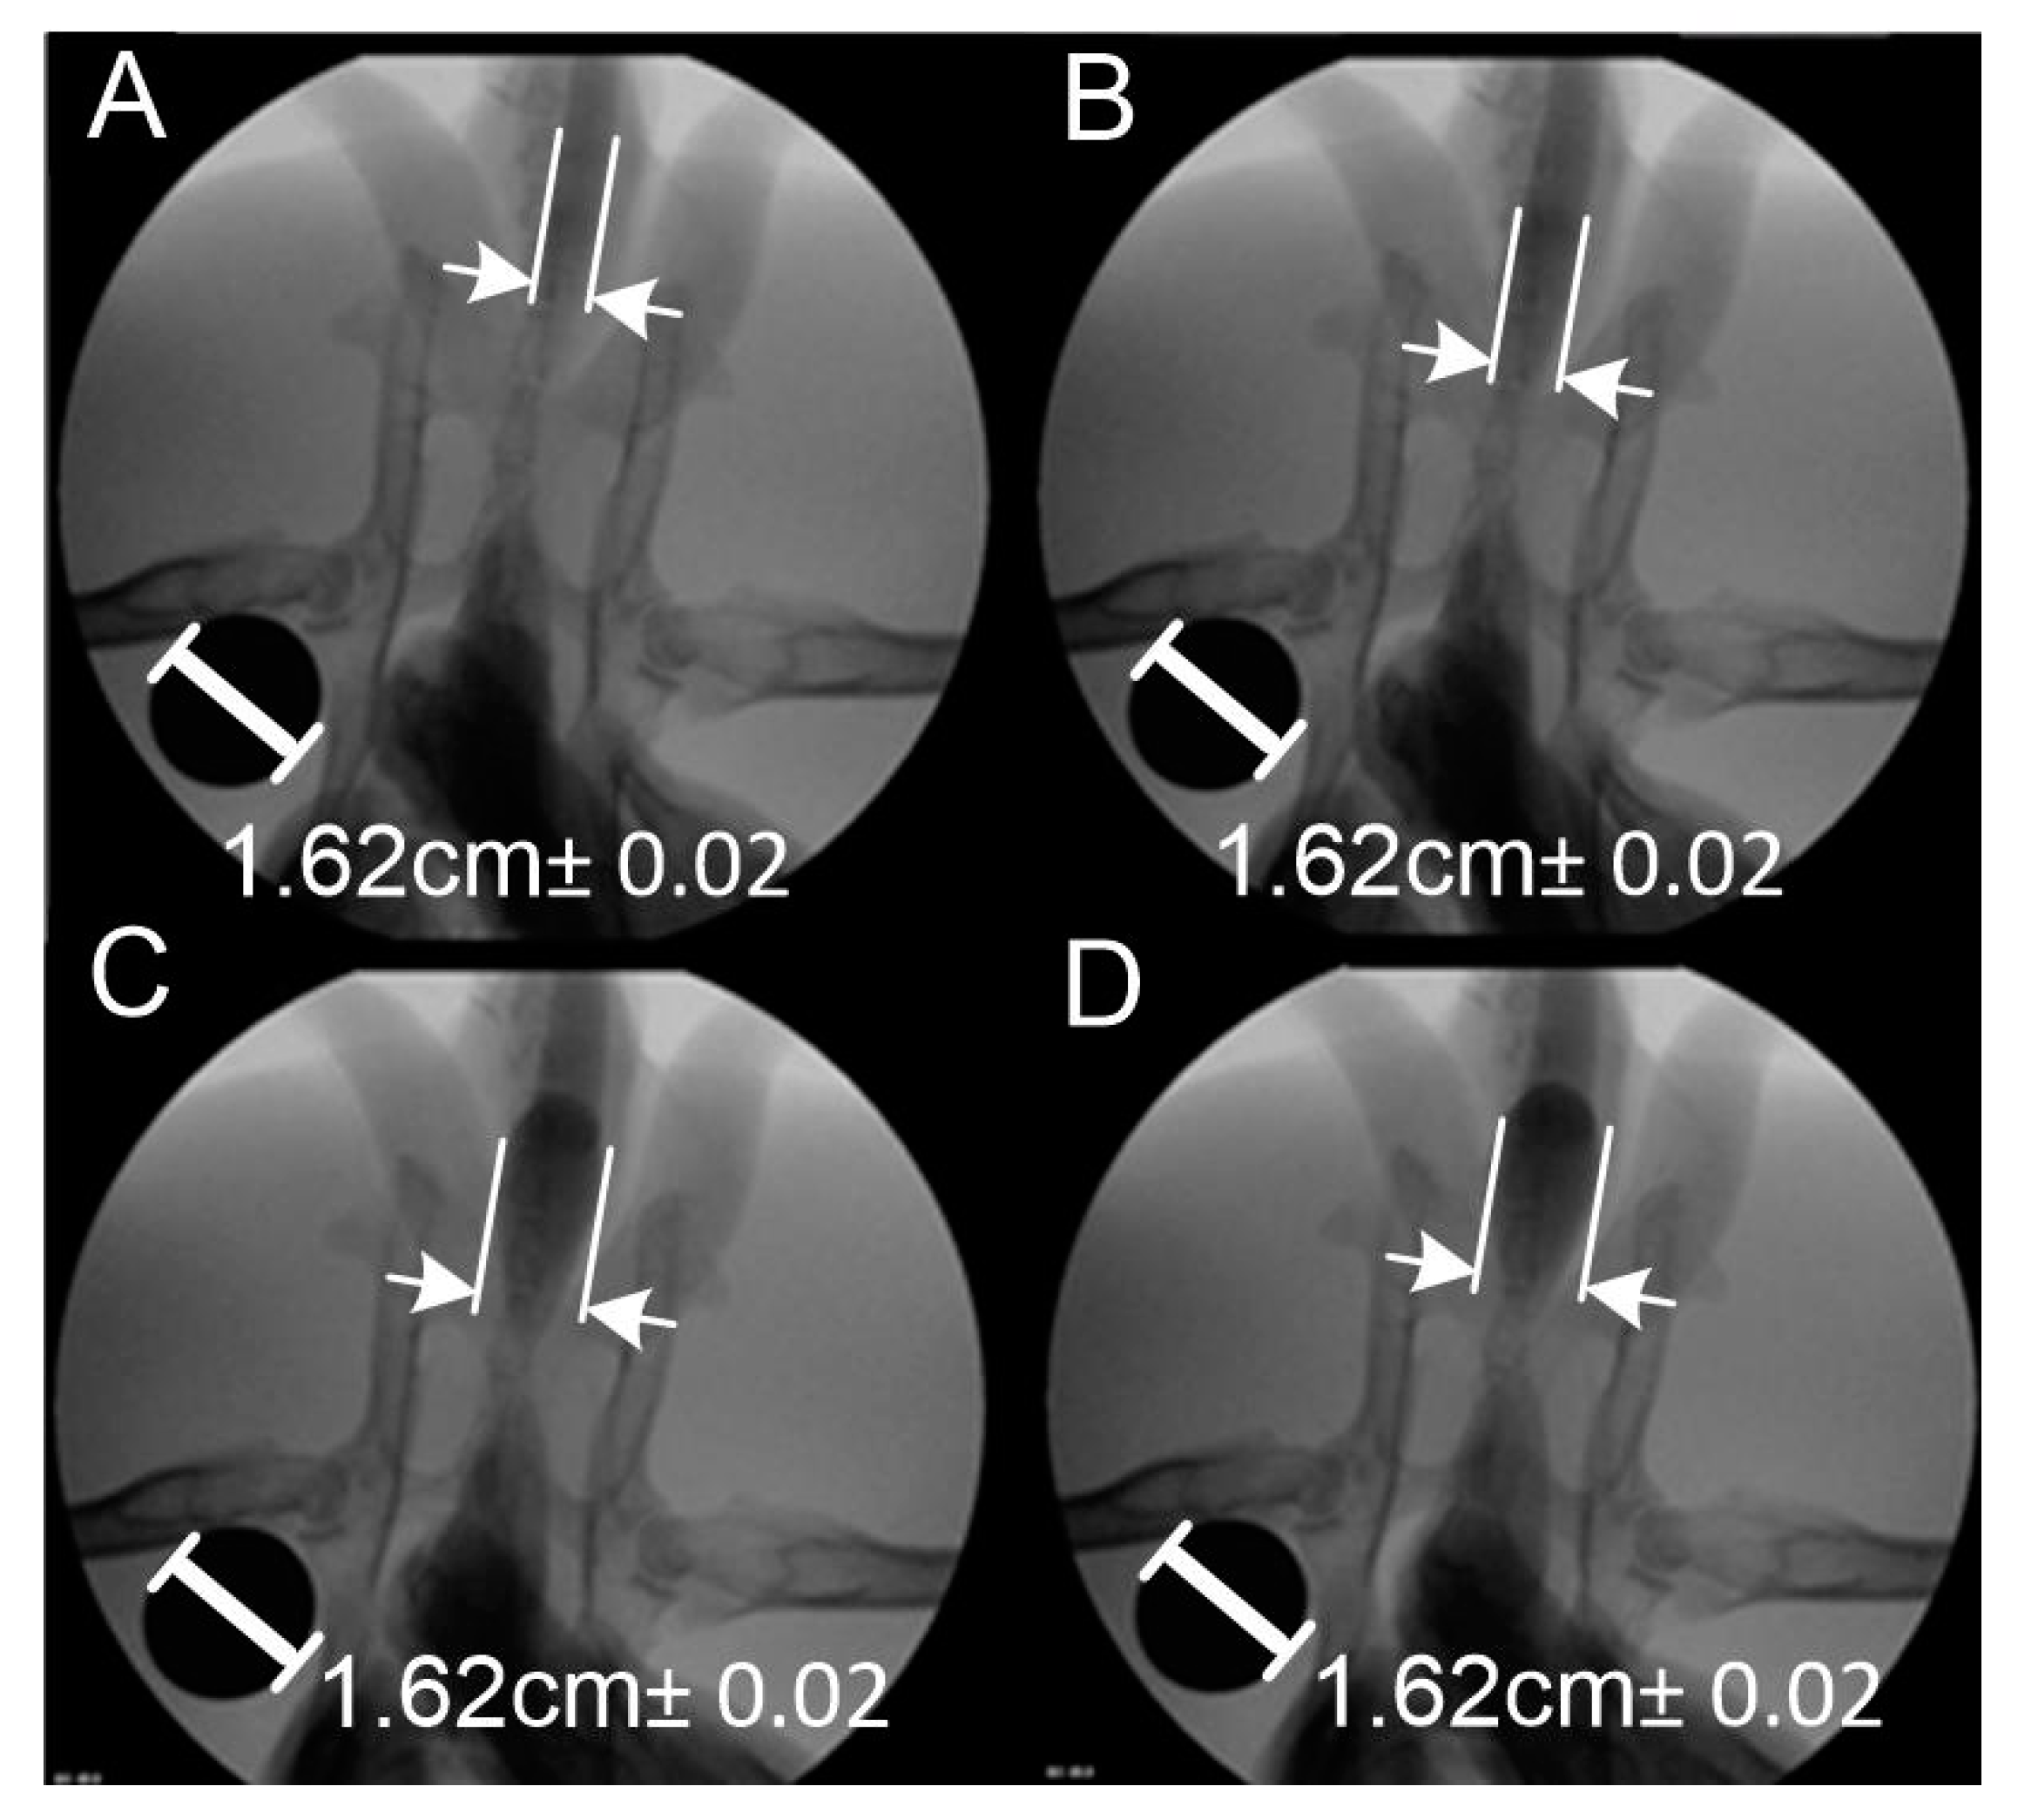

2. Materials and Methods

3. Results